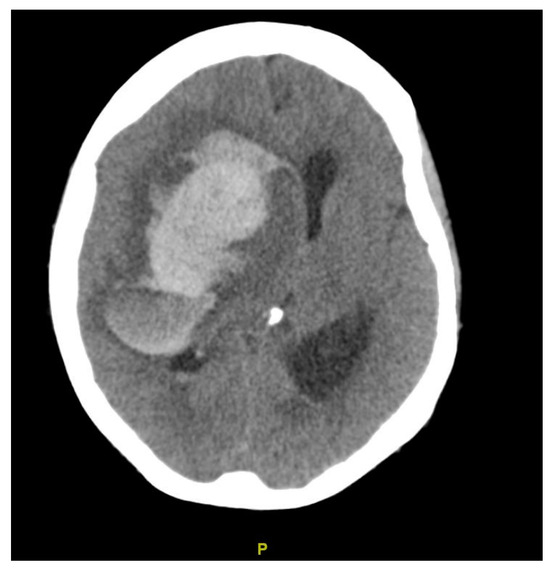

| Diagnosis | Lobar intracranial hemorrhage (ICH) | Basal Ganglia ICH | Lobar ICH | Embolic ischemic stroke (IS) | Embolic IS | |

| Clinical Syndrome | Left headache, right hemianopia | Persistent drowsiness post-OLT, GCS E1VTM2, dilated right pupil | Headache, right hemiparesis, right lower limb sensory deficits | Aphasia | Altered mental status, right gaze preference, left flaccid paralysis | |

| Imaging | CT scan | CT scan | CT scan MRI CT angiography | CT scan MRI MR angiography | CT scan CT angiography MRI | |

| Findings | CT: Left occipital intraparenchymal hematoma Volume: 15 mL | CT: Large right frontal temporal parenchymal hematoma, severe surrounding mass effect with leftward midline shift, right uncal herniation Volume: 93.5 mL | CT: Right frontoparietal parenchymal hematoma with locoregional mass effect, rightward midline shift Volume: 25 mL | CT: Left occipital infarct Transcranial doppler: 2 spontaneous emboli, more than 100 high intensity transient signals (HITS) in bilateral middle cerebral arteries (MCAs) after agitated saline | CT: Right parietal lobe hypodensity Transcranial doppler: more than 300 HITS in bilateral MCAs after agitated saline | |